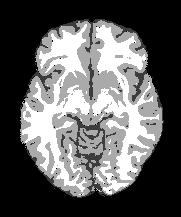

All experiments are performed on the publicly available dataset BrainWeb: Simulated Brain Database (SBD) [7]. The SBD simulator can generate MRI data of regular brain models, producing stacks of slices of pixel sizes and the corresponding ground truth for cerebral tissue segmentation. Noise and bias fields can be added by the simulator to the slice to provide realistic distortions in MRI data. Our experiments ran on all stacks of T1-weighted MRI slices using several percentages of noise (np) and bias levels (bl) to analyze the reliability of the proposed algorithm in segmenting the three ROIs under investigation. For the sake of brevity, the main results performed on four slices are discussed. The selected brain MRI slices were the number 60, 64, 91, and 100111We named the four selected BrainWeb MRIs as sliceXXX where XXX is the number of the slice with three digits shown in Table 1. Each slice appears with the corresponding ground truth and a list of the sizes of each single tissue expressed in the number of pixels and their percentage over the total.

| slice060 | slice064 | slice091 | slice100 | |

Figure 3 illustrates the workflow of the algorithm SegMIC2T using the slice060 with low (top row) and moderate (bottom row) levels of the combined artifacts. The noise estimation step splits the original MRI slice into a cartoon image (second column) and a texture image (third column) (1). The correction step, coinciding with the application of the proposed multiaffine ADMM method, produces a denoised and debiased version of the original slice, whose th pixel corresponds to (fourth column). In the last step, the segmentation of the original slice is produced by clustering the pixels in the corrected image (fifth column).